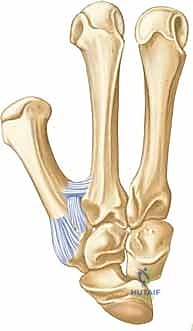

الأربطة الداعمة: حراس الاستقرار (Ligamentous Support)

نظراً لأن البنية العظمية للمفصل السرجي توفر حركة واسعة، فإنها تعتمد بشكل كبير على الأربطة القوية لمنع الخلع أو عدم الاستقرار. يتم الحفاظ على استقرار هذا المفصل الحيوي بواسطة شبكة معقدة من الأربطة، التي تعمل معاً كحبال خيمة مشدودة بدقة:

- الرباط الأمامي الراحي (رباط المنقار - Anterior Oblique / Beak Ligament): يُعد هذا الرباط الحارس الأول والأهم لاستقرار المفصل. ينشأ من الجانب الراحي للعظم المربعي ويدخل في الجانب الراحي الزندي لقاعدة المشط الأول. في حالات كسور "بينيت"، تظل شظية العظم الصغيرة متصلة بهذا الرباط، بينما يُسحب باقي العظم بعيداً.

- الرباط المائل الخلفي (Posterior Oblique Ligament): يقع في الجهة الظهرية ويعمل كرديف قوي لرباط المنقار في الحفاظ على التوازن.

- الرباط الكعبري الظهري (Dorsal Radial Ligament): يوفر دعماً وحماية ضد القوى التي تدفع الإبهام للخلف.

- الأربطة بين المشطيات (Intermetacarpal Ligaments): تربط قاعدة المشط الأول بقاعدة المشط الثاني، مما يمنع تباعد الإبهام بشكل مفرط عن باقي اليد.